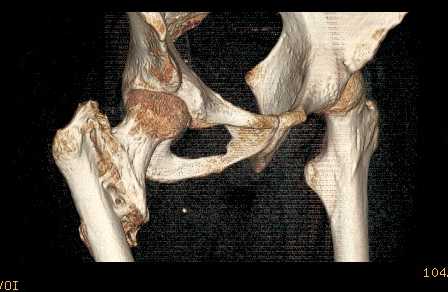

Доброго времени суток, уважаемые коллеги! Больному 45 лет. Лечили в

сельской больнице на скелетном вытяжении 6 нед. по поводу

межвертельного перелома бедренной кости с последующим наложением

кокситной повязки еще на 2 мес.

С момента травмы прошло 5 месяцев, ходит с костылями без нагрузки,

контрактуры в коленном и в тазобедренном суставах. Снимки во

вложении. У нас мнения разделились. Показанием для открытого

остеосинтеза мы считаем неустраненное ротационное смешение

дистального фрагмента, которое может привести к нарушению биомеханики

в тазобедренном суставе с последющими вытекающими последствиями. ЭОП

на сегодняшний день недоступен нам, а остеосинтез угловыми

пластинами, что можно попытаться, имеет определенный риск. Как быть?

Начать разработку в суставах и активизировать больного, что не было

сделано до этого, или всё-таки оперировать? Будем рады Вашим советам.